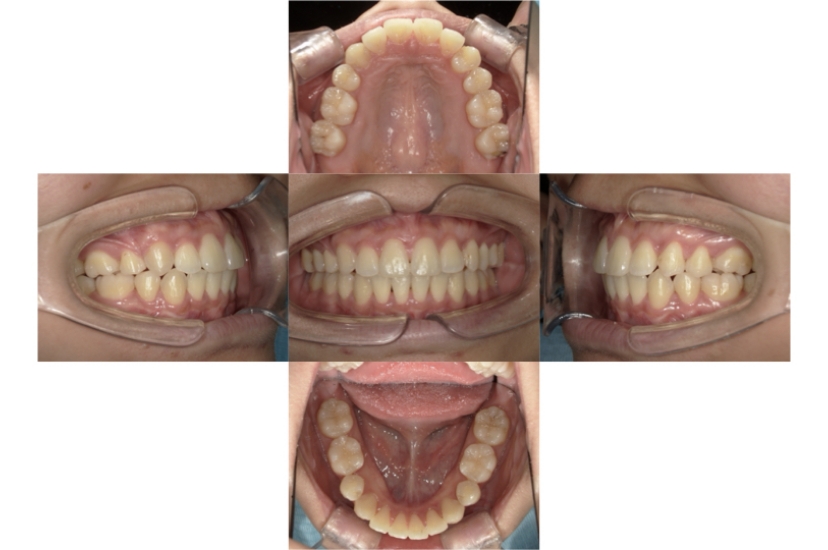

BEFORE

AFTER

上下顎叢生、上顎前突(出っ歯、上下の前歯のガタガタ)のケースです。

装置はラビアル(上下表側)で、上顎の小臼歯を2本抜歯を行っています。抜歯したスペースを使って、上の前歯の後方移動と叢生(ガタガタ)と出っ歯の改善を行っています。下は歯と歯の間にIPR(隣接面削合)を行い、スペースを確保し、叢生の改善を行っています。

主訴 前歯のガタガタと出っ歯が気になる。

年齢・性別 47歳 女性

お住まいの地域 神奈川県川崎市

治療方針 抜歯スペースおよびIPRを利用して上前歯の叢生(ガタガタ)の改善

抜歯部位 上顎左右第一小臼歯

使用装置 ラビアル(上下表側)、顎間ゴム

治療期間 2年0か月

治療回数 15回

リテーナー クリアリテーナー